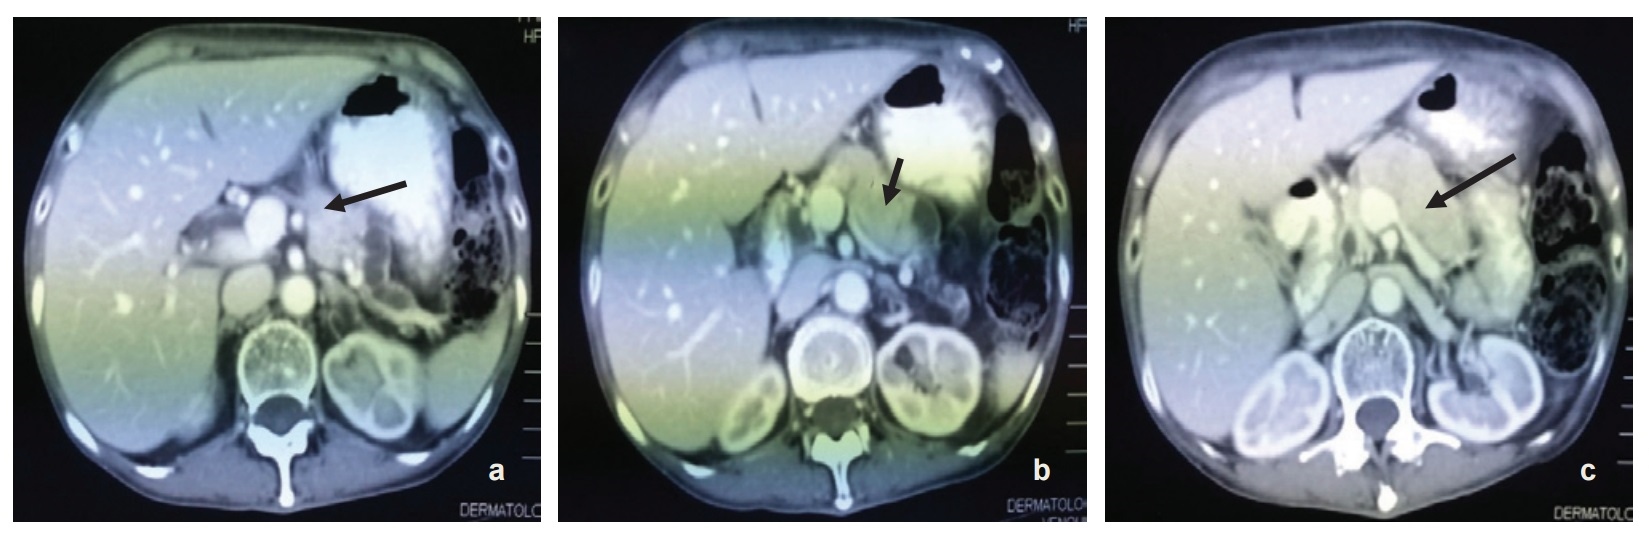

The patient was referred to the dermatology service and skin biopsy was done which revealed mild acanthosis with marked spongiosis. There was hyperkeratosis and parakeratosis as well as plasma, neutrophils and bacterial colonies on the keratin layers. The dermis shows perivascular and interstitial infiltration by lymphocytes, neutrophils and eosinophils. This findings are suggestive of infection and features are compatible with NME. Subsequently, CT scan of the abdomen was done which revealed a pancreatic neck and body tumor most likely representing glucagonoma (5.5 x 2 x 3 cm) with possible liver metastases. (Figure 2a-c). Further investigations revealed raised serum Chromogranin A >770 ng/ml (27-94) and serum glucagon of 1068 pg/ml(50-150).

Click here to download Figure 2 (a-c).Figure 2 (a-c). Radiologic findings - (serial axial view) showing tumor at the neck and body of the pancreas measuring 5.5x2x3 cm.

As illustrated in our patient case, the pancreatic tumor was readily visualised by CT scan imaging and the size was comparable with the average size of 6 cm reported in a case series.24 However, the position of the tumor at the neck and body of the pancreas was not classic for glucagonoma, which is more commonly found at the tail of the pancreas (45-75%).12 CT scan is usually the initial non-invasive radiographic test. Other imaging techniques that can be used to detect the tumor are abdominal ultrasound, MRI and selective visceral angiography.7 Selective angiography of the celiac and superior mesenteric15 arteries is the gold standard in the diagnosis and localisation of glucagonoma as this tumor shows significant hypervascularity.7 In addition, this technique is able to demonstrate hepatic metastases even in a patient with a negative liver scan.7 The role of pancreatic venous sampling for glucagon levels in the diagnosis of small tumor has been reported.8 As a result of subtle and non-specific manifestations, glucagonoma is usually diagnosed late with metastatic spread on diagnosis6 and in this patient's case, liver metastases. The liver is the most common site for metastasis. Most of the time, the metastases are multiple, involving many hepatic segments and are variable in size.6 Other common sites for metastases are regional lymph nodes, bone, adrenal gland, kidney and lung.25,26